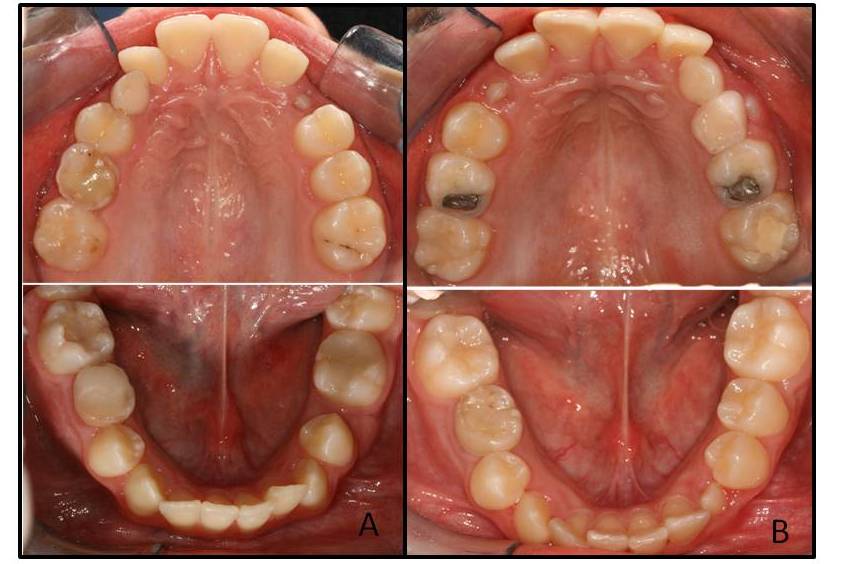

Molar-incisor hypomineralisation is a qualitative defect of dental tissue of systemic origin affecting one or more permanent first molars and sometimes the permanent incisors as well. There are still no conclusive data on the aetiology of this hypomineralisation, however, systemic factors such as respiratory diseases and prenatal and perinatal complications are regarded as possible causes. The objective is to present three clinical cases of twins, one Monozygotic Twins , and two Dizygotic Twins with molar-incisor hypomineralisation, besides showing evidence of its manifestation as well as clinical the characteristics and aetiological factors involved. The clinical findings involving twins show that ameloblasts are specifically affected in their developmental phase, which includes a number of factors although prenatal and perinatal complications not decisive in the development of molar-incisor hypomineralization and suggest a possible genetic susceptibility to the disease. Prospective observational studies using a population sample containing data on the last three months of gestation to the eruption of permanent teeth are needed to confirm the cause-effect relationships.